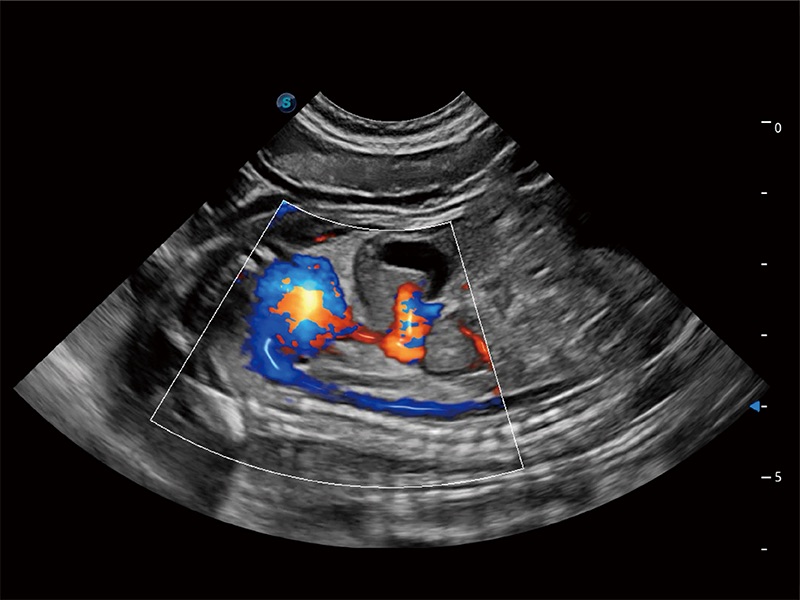

高性能和先进的临床应用工具可以为动物医生提供临床信心。ProPet 80 搭载了先进的腹部和浅表应用工具,帮助医生在日常临床实践中发挥前所未有的作用。

非线性融合造影成像充分利用谐波和基波信号,为难以观察的血流进行增强显像。可用于线阵、凸阵、微凸阵、相控阵探头。